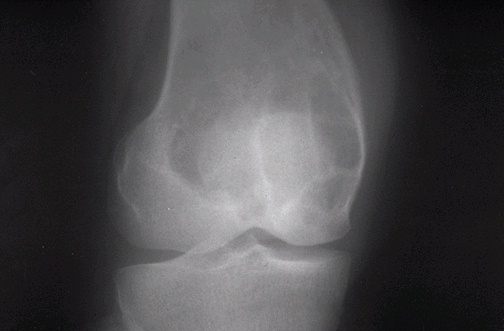

Radiographs show an expansile, eccentric lesion located in the metaphysis of the distal femur that is surrounded by a rim of reactive new bone as a host response.